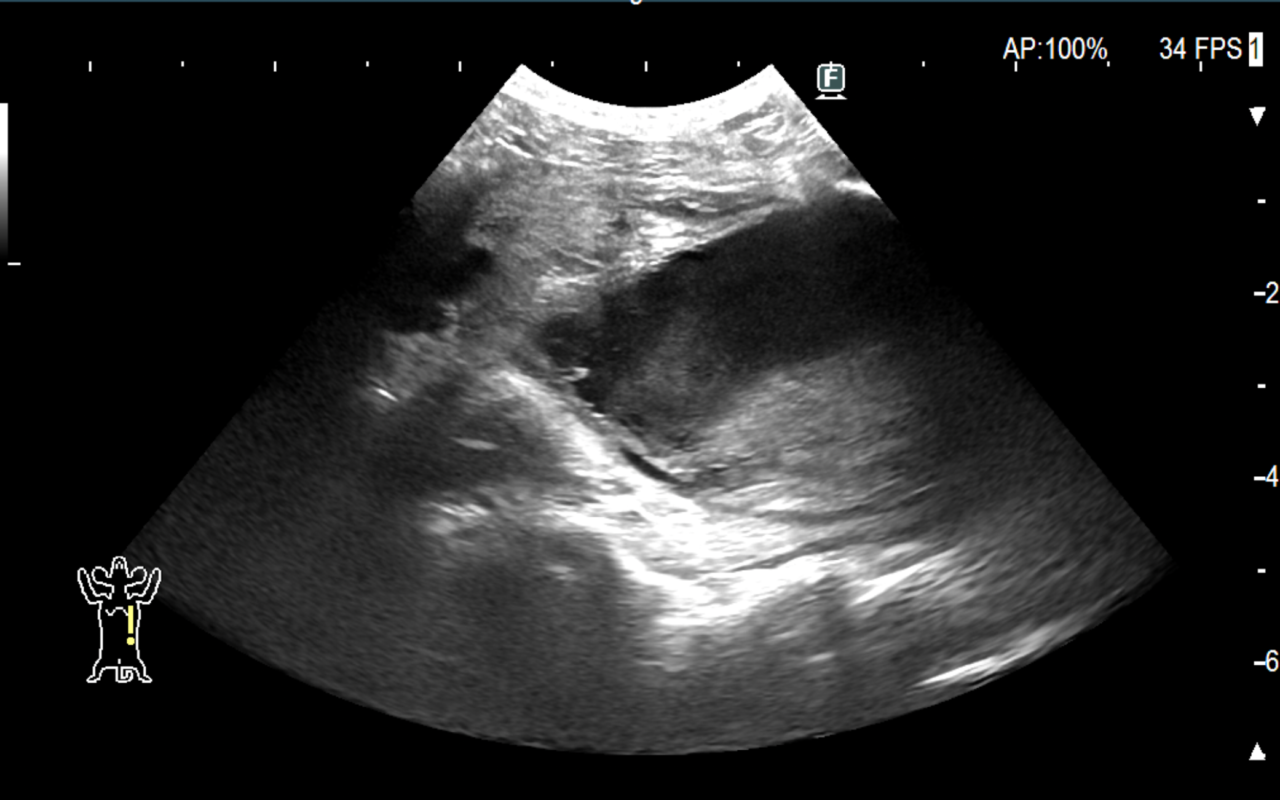

腹部超音波検査では前立腺実質エコーは均質であり、形状は通常左右対称である。前立腺炎の場合、実質は不均一であり、多巣性の低エコー領域が存在する。前立腺膿瘍および前立腺内嚢胞は局所的な単一または複数の無から低エコーの構造として現れる。